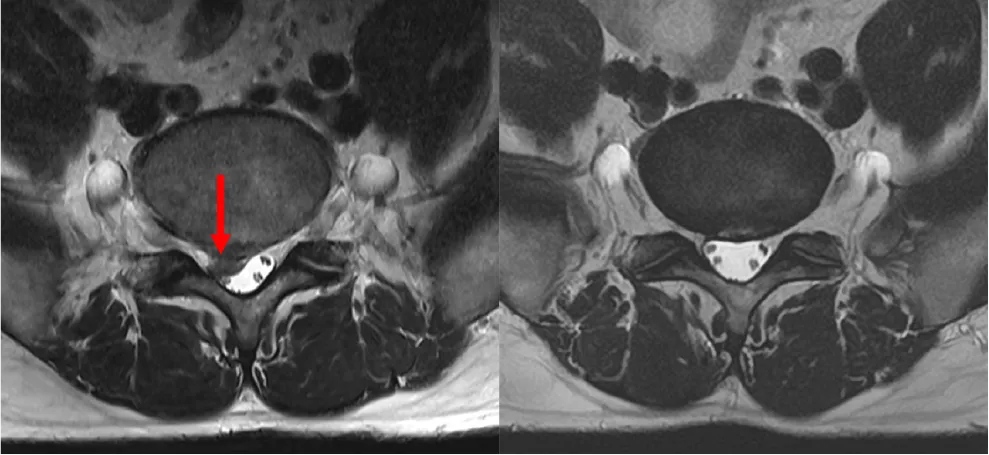

頚椎症性脊髄症に対する椎弓形成術

-

術前MRI

術後MRI